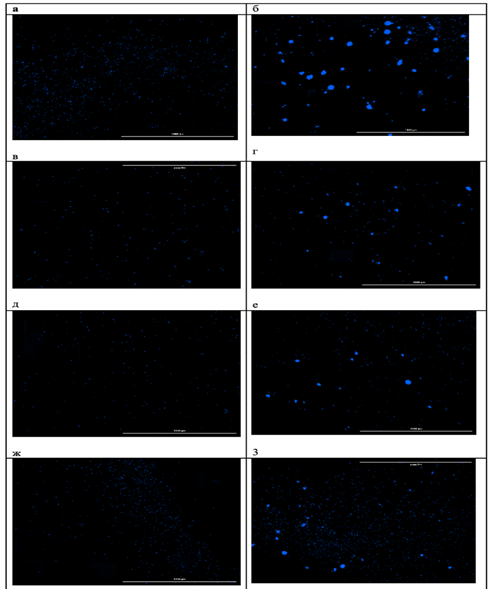

При исследовании чувствительности мононуклеарных клеток периферической крови к берберинуin vitroбыло выявлено стимулирующее влияние берберина на их пролиферативную способность, проявлявшееся увеличением количества и площади формируемых колоний. При этом благоприятный клинический исход ассоциировался не с более высокой базальной колониеобразующей активностью, а с формированием более крупных колоний, что может отражать наличие лимфоцитарных клонов с более высоким пролиферативным и метаболическим потенциалом. Это позволяет предположить, что прогностическое значение может иметь не общее число клеток, а качественные характеристики клонального пролиферативного ответа (рис.3, 4).

Рис.4. Микрофотографии образовавшихся колоний мононуклеарных клеток периферической крови пациента с неблагоприятным исходом: а – контрольная проба, б – контрольная проба с добавлением ФГА, в – проба с добавлением 1мкмоль/л берберина, г – проба с добавлением 1мкмоль/л берберина и ФГА, д – проба с добавлением 2мкмоль/л берберина, е – проба с добавлением 2мкмоль/л берберина и ФГА, ж – проба с добавлением 4мкмоль/л берберина, з – проба с добавлением 4мкмоль/л берберина и ФГА.

Примечание: составлен авторами по результатам данного исследования

У пациента с благоприятным клиническим ответом изначально отмечалась более низкая базальная колониеобразующая активность МНПК: количество колоний было на 56% меньше по сравнению с пациентом с рефрактерным течением заболевания, однако их средняя площадь превышала данный показатель на 22%. Воздействие берберина в исследованных концентрациях вызывало дозозависимое усиление колониеобразующей способности МНПК у обоих пациентов, при этом наибольшая стимуляция наблюдалась при сочетанном применении берберина и фитогемагглютинина, что свидетельствует о синергическом эффекте изучаемого соединения с митогенной стимуляцией (рис.5, 6). Использование ФГА позволило оценить влияние берберина в условиях активированной иммунной реакции, что приближаетмодель in vitro к условиям реализации противоопухолевого иммунного ответаin vivo.

Кроме того, были выявлены индивидуальные различия в чувствительности МНПК к берберину: у пациента с полным ответом на терапию наибольшее увеличение количества колоний наблюдалось при концентрации 1мкмоль/л, тогда как у пациента с неблагоприятным исходом пик пролиферативного ответа смещался на 2мкмоль/л (рис.5). Полученные различия могут объясняться особенностями метаболической и пролиферативной активности отдельных лимфоцитарных клонов. Более крупные колонии у пациента с благоприятным исходом могут отражать наличие клонов с высоким метаболическим потенциалом и способностью к интенсивному клеточному делению, тогда как большее число, но мелких колоний у пациента с неблагоприятным исходом может соответствовать функционально менее активным клональным линиям.